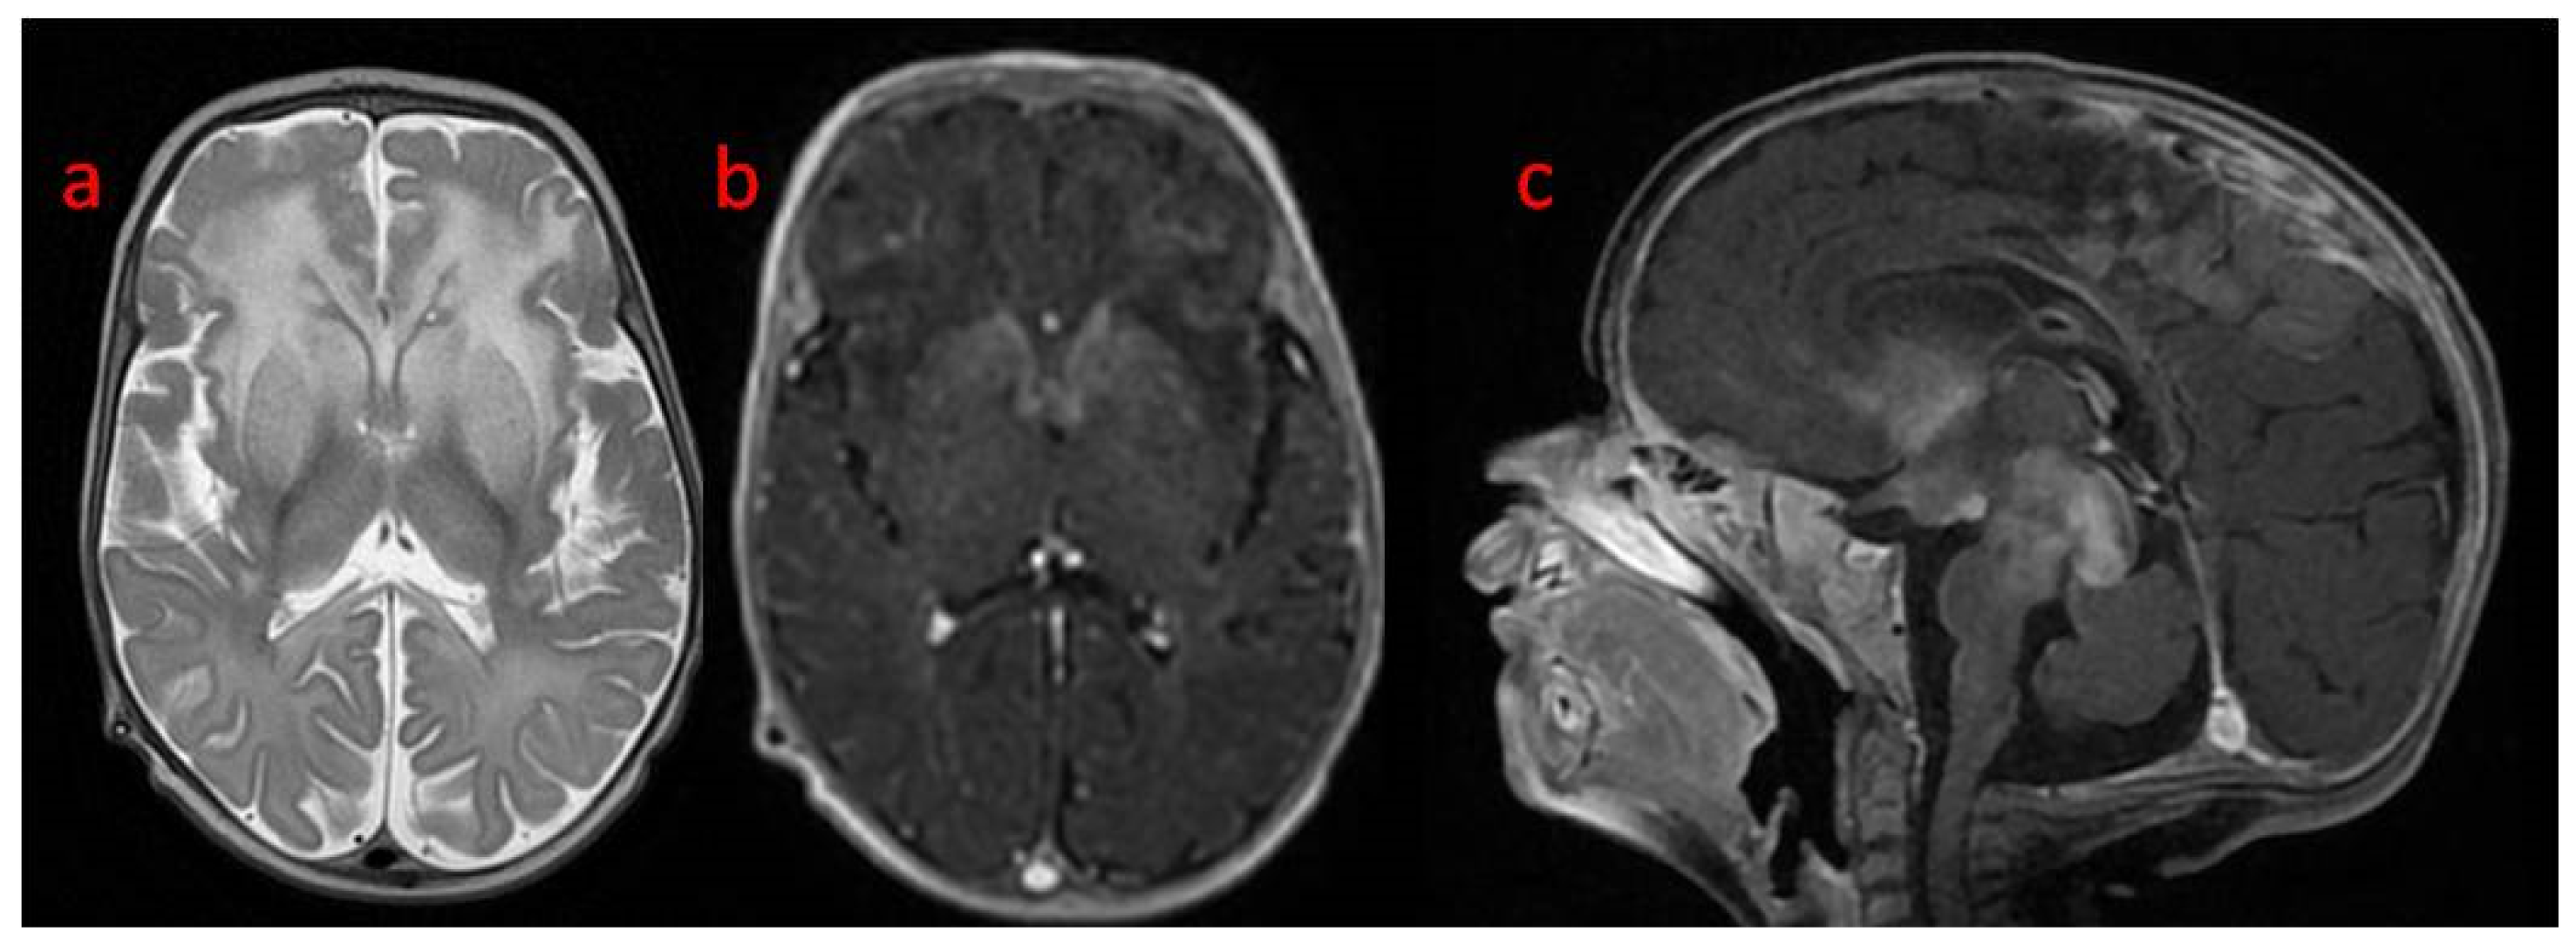

In the first weeks of life, the child presented with increasing apathy, severely limited spontaneous activity, and a lack of eye tracking. At the age of 5 weeks, a physical examination revealed the bulging frontal fontanelle and separation of the cranial sutures. A transfontanelle ultrasound examination showed a significantly enlarged supratentorial ventricular system with a ventricular index of 0.57 (N: 0.2–0.25). Signs of increased intracranial pressure led to ventriculoperitoneal shunt implantation. The surgery resulted in the resolution of the dehiscence of the sutures with limited improvement of the neurological state. MRI of the brain performed after neurosurgery revealed decreased T1 and increased T2 white matter signals in both hemispheres with frontal domination, midbrain, cortico-spinal tracts, and enlarged basal ganglia with heterogenous signals and enhancement. DWI (diffusion-weighted imaging) showed generalized abnormality and an even signal with increased diffusivity in the frontal white matter (Figure 1). In a 1-week follow-up, white matter signal changes were generalized, and symmetrical periventricular spaces in internal capsules were shown (Figure 2).

A follow-up brain MRI showed the progression of the abnormal, diffused, increased signal of white matter with frontal domination. Moreover, periventricular narrow bands of high T1 and low T2 signals, inhomogeneous signals from the basal nuclei with the most intense changes in the heads of the caudate nuclei, lenticular nuclei, and anteromedial parts of the thalamus, were observed. The examination also revealed post-contrast enhancement of subcortical nuclei and along the cortico-spinal tracts (Figure 3 and Figure 4).

Figure 2. Brain MRI control after 1 week: (a,b) coronal T2: more generalized white matter T2 hyperintensity with a low signal rim around ventricles, marked symmetrical perivascular spaces in internal capsules; (c) sagittal T1 with an abnormal signal in cortico-spinal tracts in the brain stem; (d) axial DWI: slightly better signal differentiation with generally abnormal diffusivity.